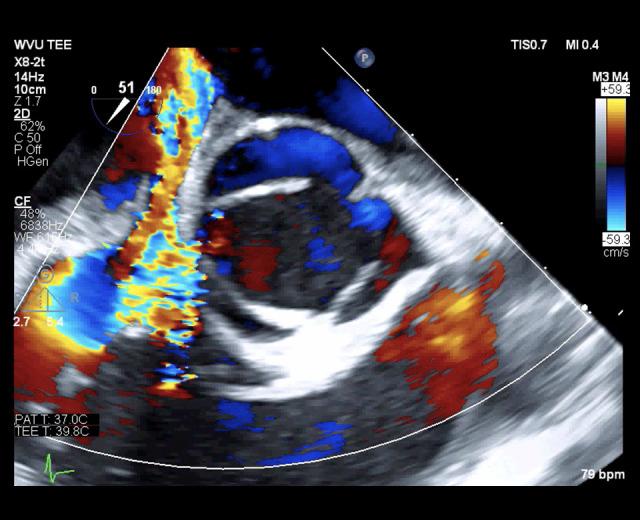

一位 34 岁男性静脉药物使用者,第三次三尖瓣心内膜炎发作,经重复瓣膜手术治疗。

A 34-Year-Old Male Intravenous Drug User with a Third Episode of Tricuspid Valve Endocarditis Treated with Repeat Valve Surgery.

病例报告

一名 34 岁男性,有静脉注射毒品史,因感染性心内膜炎在不到 7 个月的时间内进行了 3 次三尖瓣手术。他说他在第一次手术前没有注射过毒品,他有一个强大的社会支持系统,并且每次都完成了术后抗生素治疗方案。然而,在他最后一次手术前,患者的尿液药物筛查呈阿片类药物阳性,而没有记录的阿片类药物处方。3 次术中标本的病理报告显示每次都有不同的病原体。随后进行了广泛的跨专业讨论。